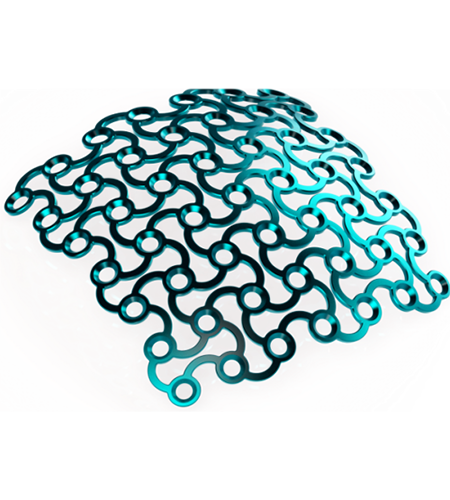

Implant material

- Commercially pure titanium

- Ultra-high strength

- Excellent biocompatibility

- Radiopaque

- Autoclavable – withstands repeated sterilization

- Requires the use plates and screws are used to attach the patient specific implant to native bone.

Material selection and manufacturing

The material is selected, according to medical and technical aspects; manufacturing is carried out in our modern fabrication centere.